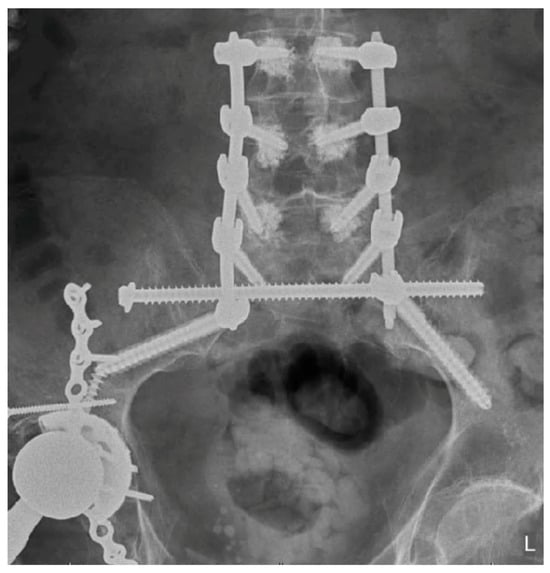

Minimally Invasive and Navigation-Assisted Fracture Stabilization Following Traumatic Spinopelvic Dissociation

5. Techniques and Considerations in Spinopelvic Fixation: Sequence, Reduction, and Avoiding Complications

6. Spinopelvic Fixation Percutaneous Technique

7. Tran-Sacral Percutaneous Technique